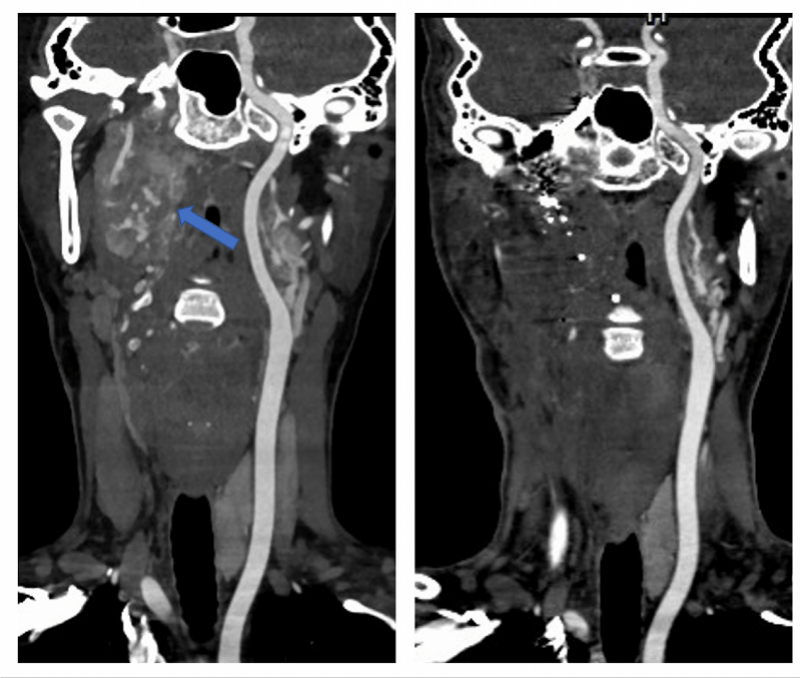

入院后 , 刘女士完善了CT(电子计算机断层扫描)和MR(核磁共振)检查 , 从影像资料可看到 , 刘女士的右颈部肿瘤已向颈部深处生长 , 肿瘤不仅侵犯右颈动脉及颈静脉导致其完全闭塞 , 还环绕着右颈动静脉向上生长 , 经过颈静脉孔到达颅底 。

手术前后的CT影像对比:左图为术前 , 箭头指示为肿瘤;右图为术后 , 显示无肿瘤残留